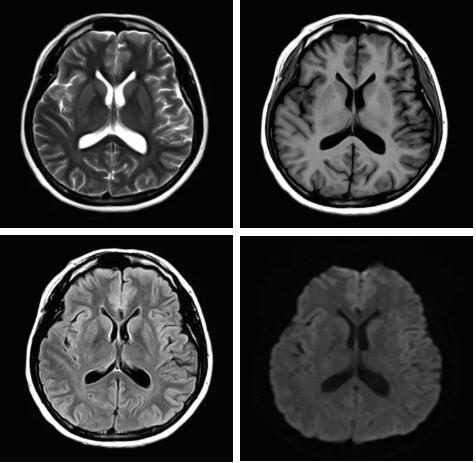

圖:Pure射頻成像鏈的優(yōu)化和改進(jìn)使信噪比提升